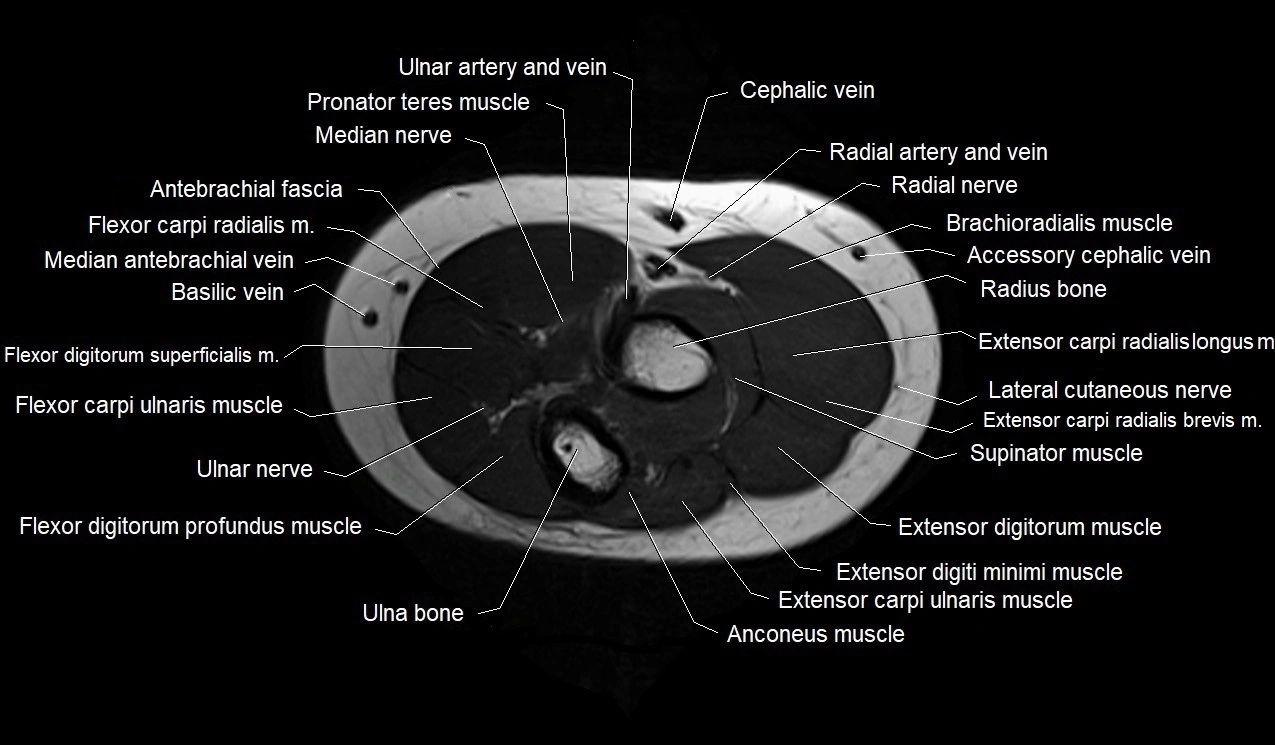

MRI images

image